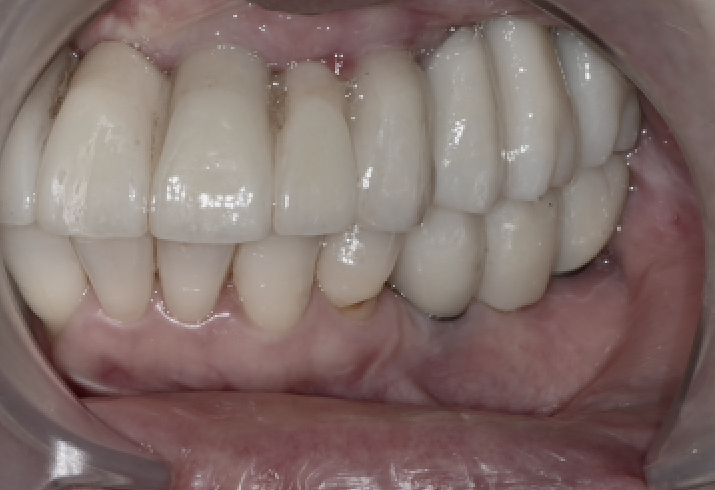

최종 지르코니아 보철 장착

충분한 조정을 거쳐

최종 지르코니아 보철을 장착했습니다.

앞니 라인부터 어금니 라인까지

자연스럽게 이어지도록 디자인했고,

씹는 힘이 한쪽으로 치우치지 않도록

교합을 세밀하게 조정했습니다.

이 과정에서 환자분은

“전체적으로 씹는 힘이 균형 있게 들어간다”고

말씀해주셨습니다.

장착 후 3개월 체크

전체임플란트 수술

3개월 뒤 다시 내원하셨을 때

임플란트와 보철물, 잇몸 모두

안정적인 상태였습니다.

왼쪽이 조금 덜 씹힌다는 느낌이 있어

교합면을 아주 미세하게 조정해드렸고,

그 이후에는 편안하게 사용하고 계십니다.